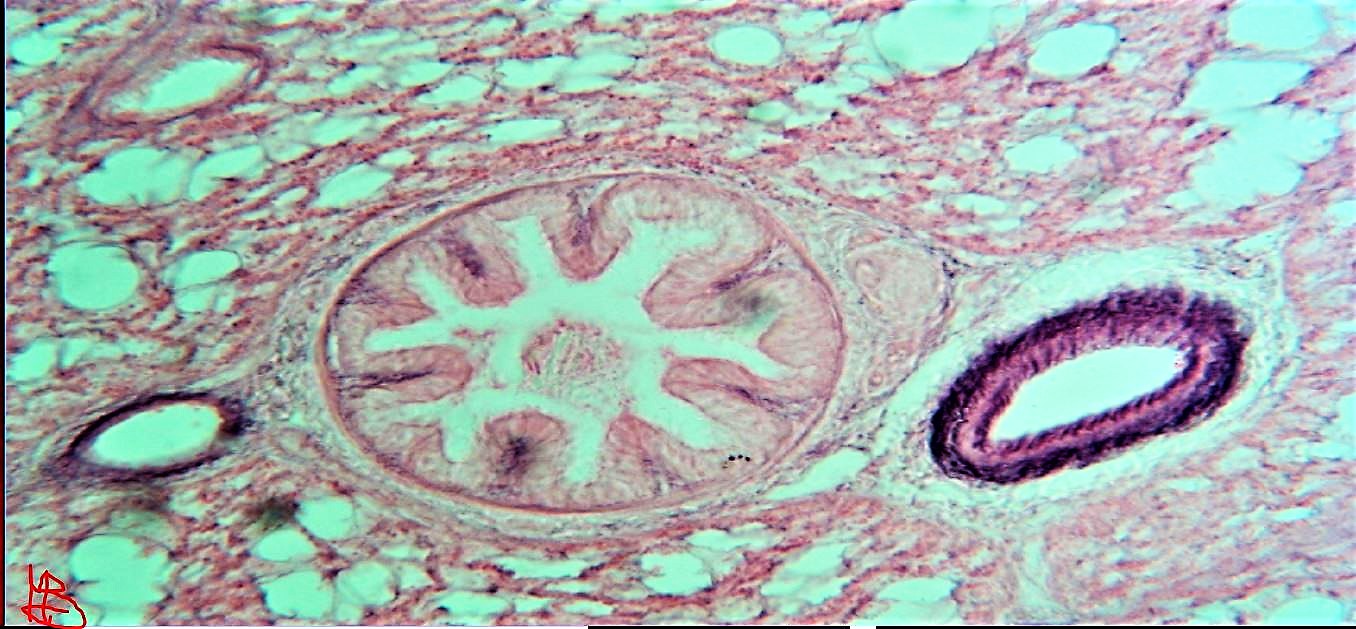

come giustamente dice Marcopic non c'è molta differenza dal piccolissimo al grandissimo perché tutto è relativo!!senza telescopio l'universo è piccolissimo e non si vede tal quale il micromondo che senza microscopio non si vede. non darti fretta per le opportunità ottiche del micro . inizia in campo chiaro! poi scuro. poi polarizzazione poi dic e avanti così. hai un buon micro! e appena Enotria ti leggerà saprà darti consigli!! ci sono molte pagine dedicate al "Micromondo" gironzola in web! la mia si chiama appunto "Micromondo" dove mi vanto ci siano microscopisti eccezionali! e anche qualche scienziato di fama. datti tempo!ben venuto in un mondo incredibile!!quella che ti posto è un immagine da un vetrino del 1905!! micro sezione di bronchiolo e capillare circa 700 x. divertiti.con pazienza!

Immagine:

Presentazione.

239,33 KB